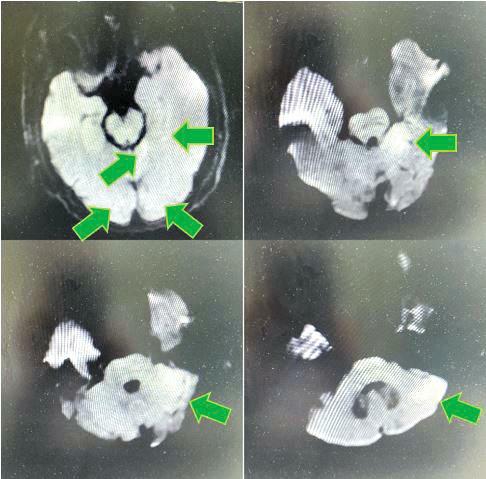

术中从基底动脉尖取出的血栓

王虎清教授立即查看患者,与患者家属充分沟通取得同意后,神经内科介入团队其他成员范清雨主治医师、张宏医师、蒋鹏鹏护士迅速到位,导管室迅速启动,在麻醉科代志明医师的协助下为该患者进行了脑血管造影,造影证实患者基底动脉远端闭塞,同时合并右侧椎动脉闭塞,左侧椎动脉开口及V4段线样狭窄、颅内段显影不佳。神经内科介入团队医师经严谨讨论后,考虑患者目前病情危重,给予基底动脉尖负压抽吸取栓,一把完全再通,患者基底动脉血流恢复,双侧大脑后动脉及小脑上动脉显影良好。考虑患者右侧椎动脉闭塞,左侧椎动脉开口及V4段线样狭窄,仍有发生栓塞及椎基底动脉闭塞的风险,遂继续行椎动脉开口及V4段球囊扩张+支架成形术,术程顺利,手术结束时已是10月29日的凌晨。